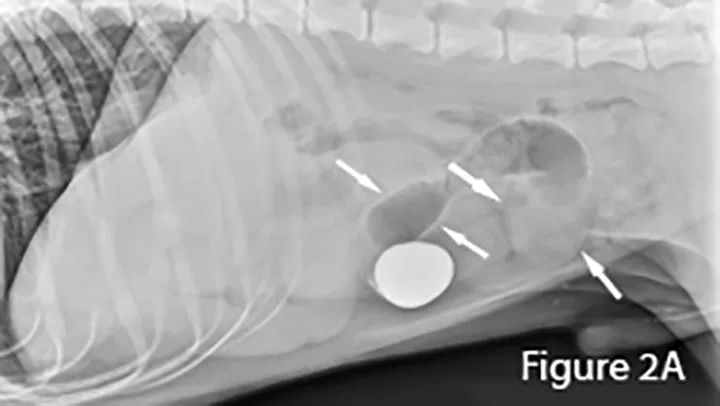

A foreign body (ie, rock) is identifiable in this canine small intestine. The markedly dilated segment of jejunum (arrows) leading up to the foreign body (~4× the height of L5) is significant.

Lateral abdominal radiograph of a dog with small intestinal obstruction. There is marked segmental small intestinal dilation (arrows) with heterogeneous soft tissue and mineral opaque material in the lumen. The cause (ie, the mass) is not identifiable radiographically; there is a large amount of normal empty small intestine.